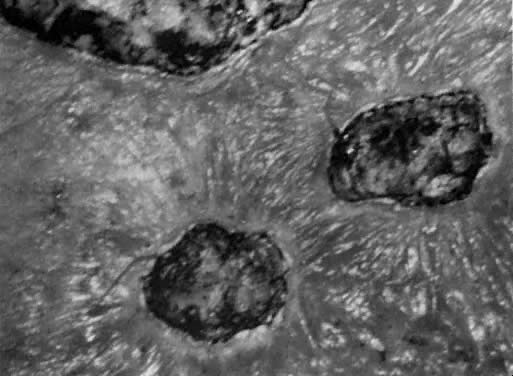

Local anesthesia may be used for small isolated vulvar warts. However, with more extensive disease, general anesthesia is preferred. Warts should be vaporized no deeper than the level of the surrounding skin surface (Fig. 21, Fig. 22, and Fig. 23) using a power level of 40 W to 60 W with a beam diameter of 3 mm. After complete vaporization of the genital warts is accomplished, the 1 cm to 2 cm of skin surrounding the individual lesions is brushed lightly with 10 W of power and a 2-mm-diameter spot size to destroy subclinical HPV involvement and diminish the recurrence of the disease. When the condyloma lesion has a well-defined pedicle, it is more efficient to excise rather than vaporize the entire lesion. Ablation of the remaining base is then accomplished to the level of the skin surface. The postoperative treatment regimen is identical to that described for VIN. Laser treatment of genital warts is effective; they are eliminated in over 90% of patients. For those patients who are immunologically compromised, chronic application of 5-fluorouracil cream has been recommended.22 The use of recombinant interferon after laser treatment by Reid and colleagues has also diminished their recurrence.23

Fig. 23. Condylomatous skin change as viewed under the microscope is brushed with the laser to vaporize only the epithelium. Gross warts are vaporized to a depth of 1 mm.